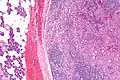

| Micrograph of an acinic cell carcinoma (right of image) and acinar glands (parotid gland - left of image). H&E stain. | |

Basophilic, bland cells similar to acinar cells. Growth pattern: solid - acinar cells, microcytic - small cystic spaces mucinous or eosinophilic, papillary-cystic - large cystic lined by epithelium, follicular - similar to thyroid tissue.

These tumors, which resemble serous acinar cells, vary in their behavior from locally aggressive to blatantly malignant.